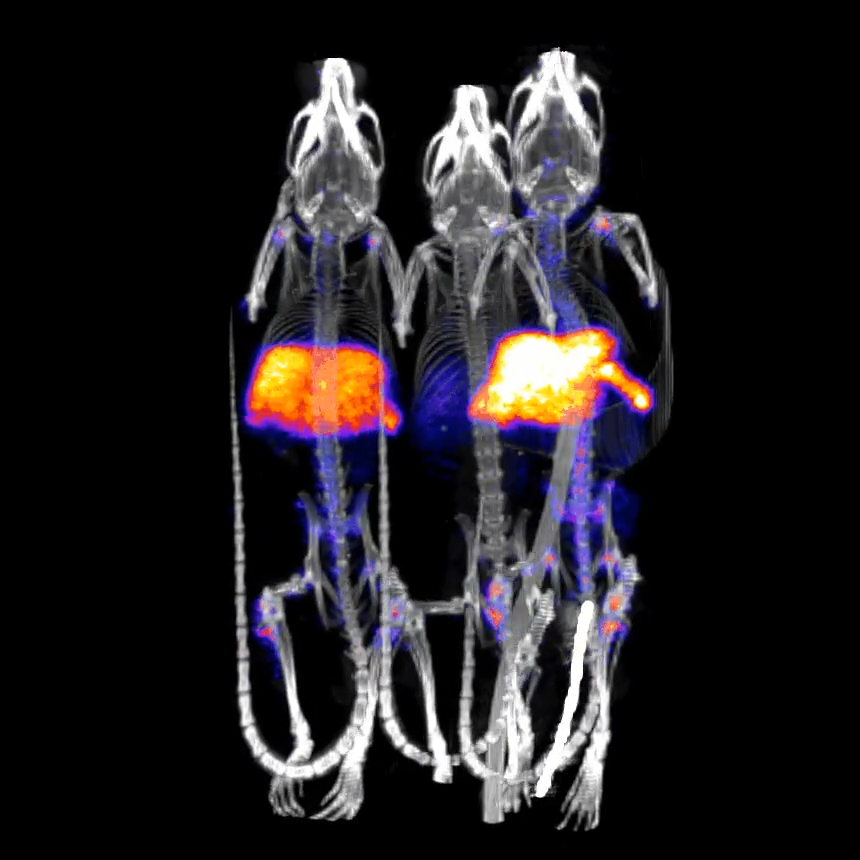

体内细胞追踪采用Zr-89

细胞追踪长期随访研究的最后时间点。注射后17天进行成像。

〉实验动物:3只体重20克的小鼠

〉放射性示踪剂:30kBq(0.8μCi)的Zr-89标记细胞

〉采集方式:静态PET扫描